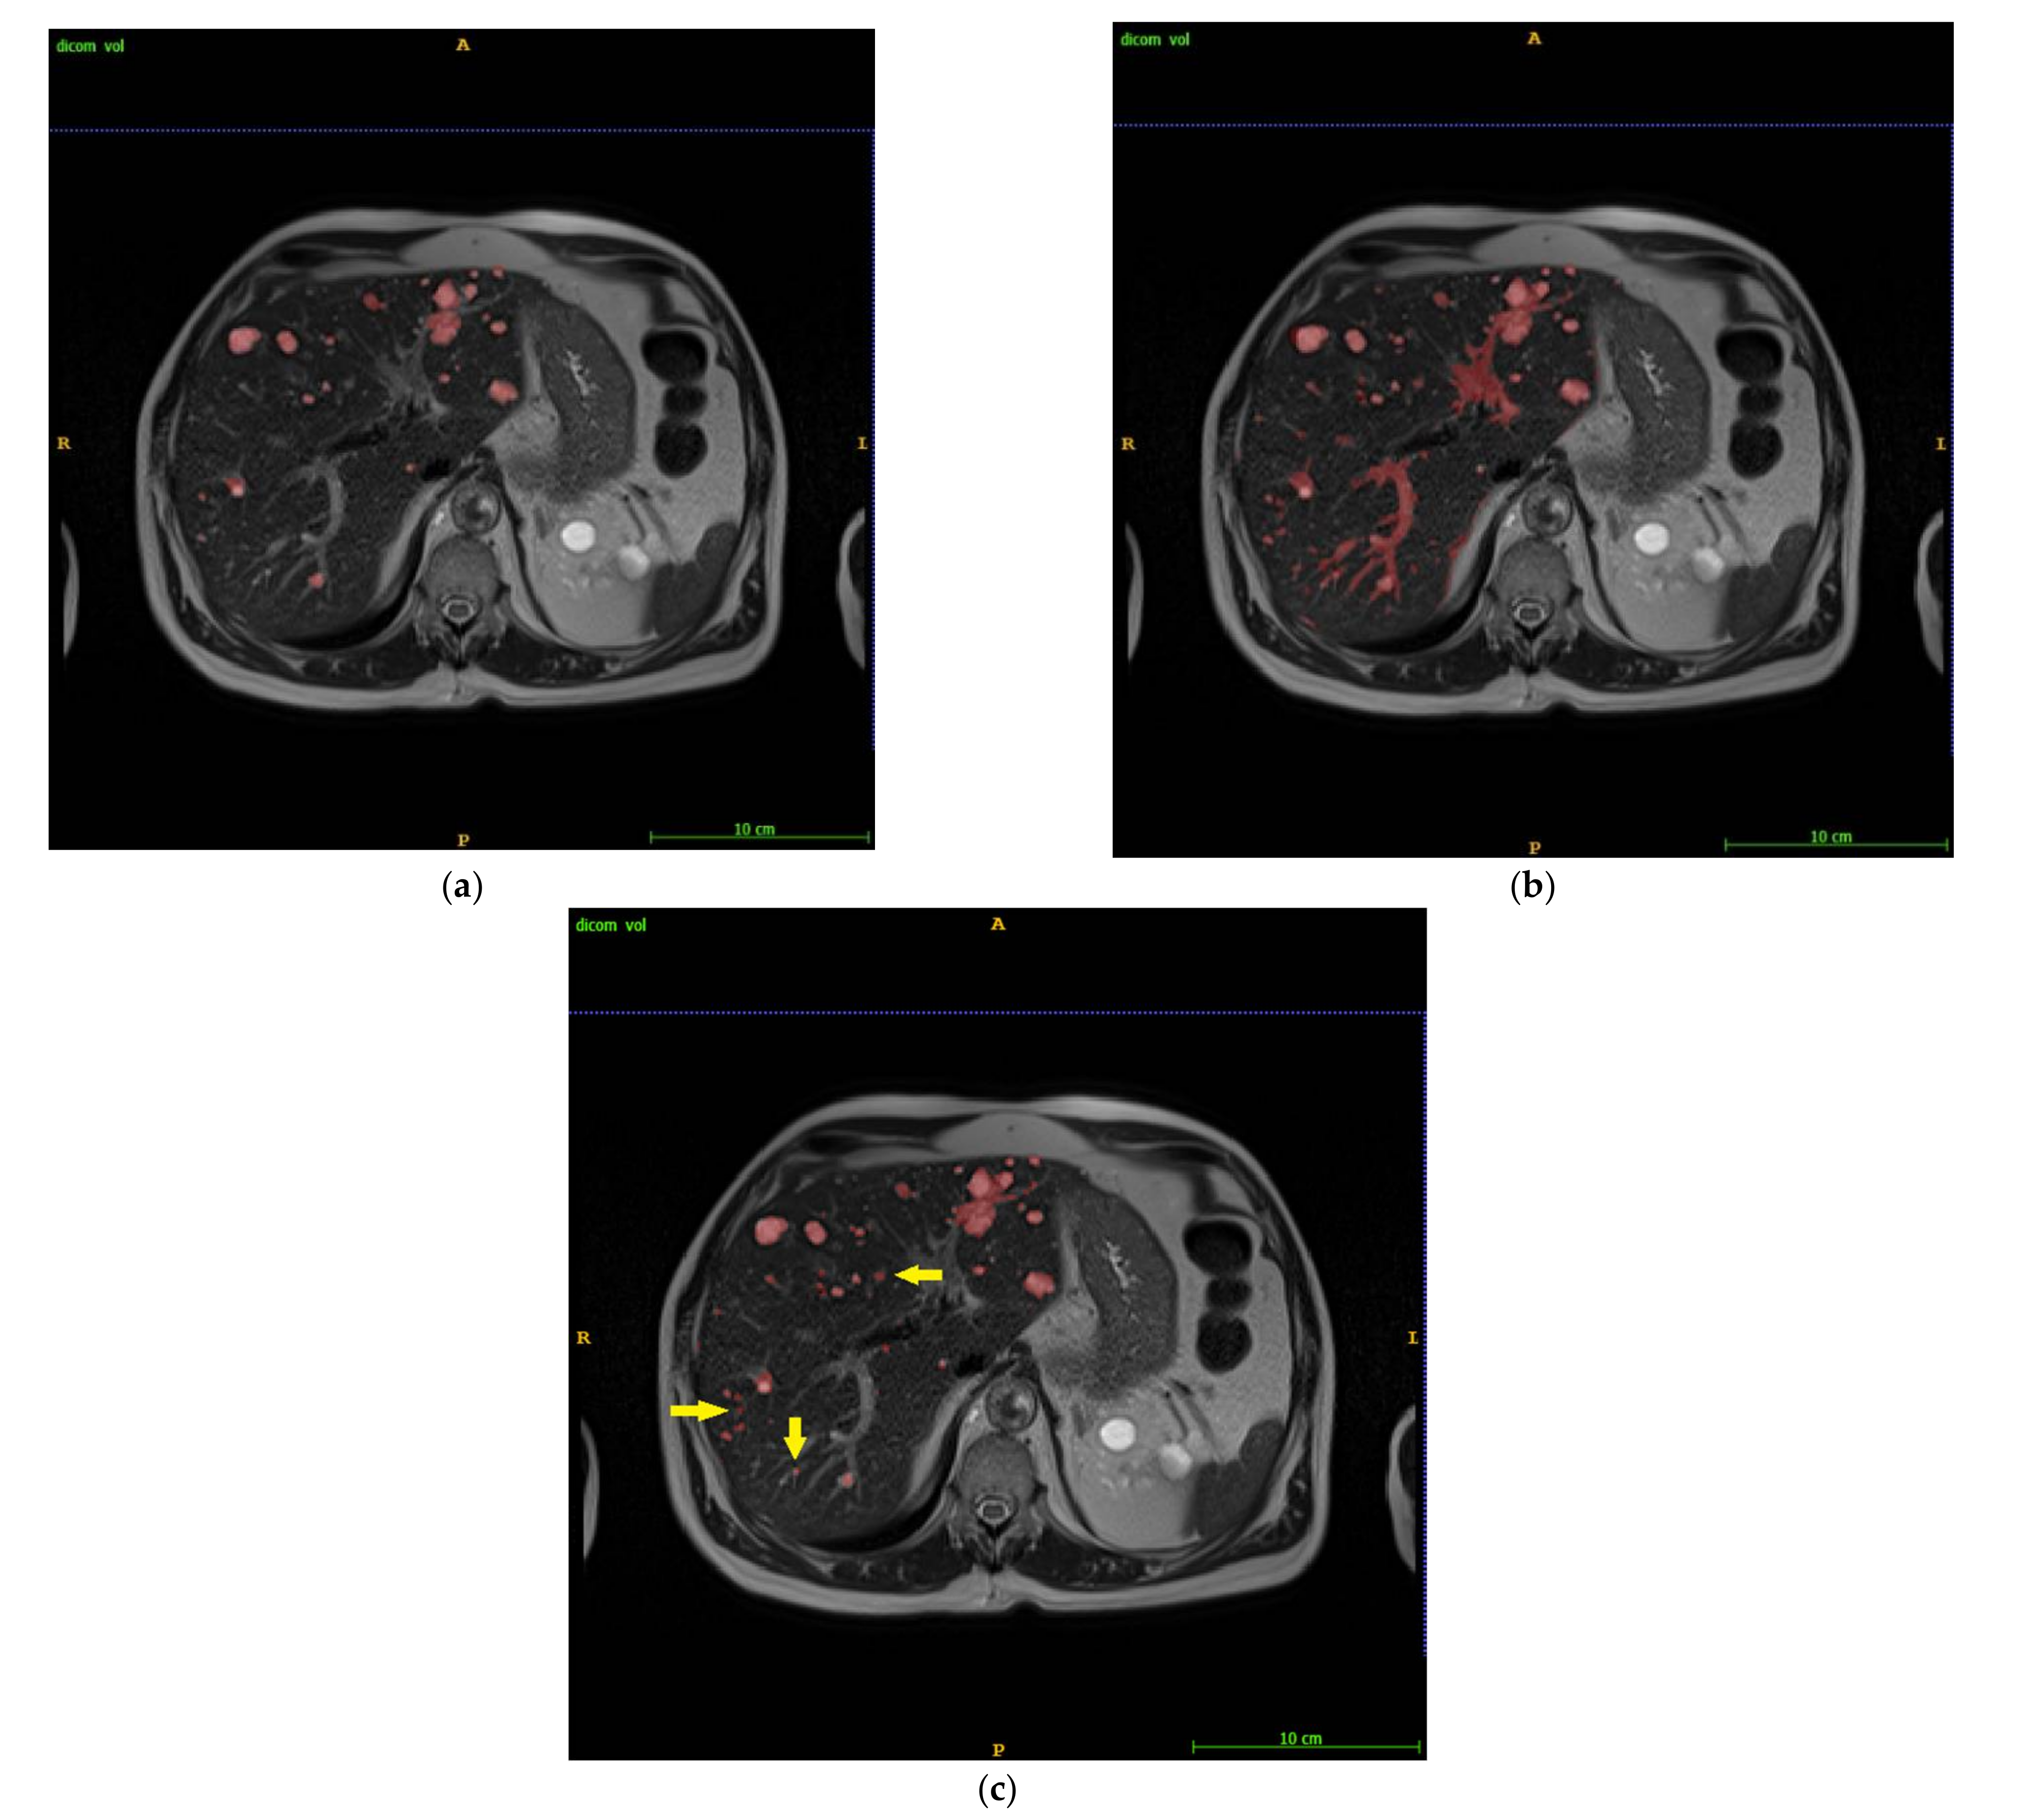

2.1. Intelligent Rapid Interactive Segmentation (IRIS) Method and Implementation